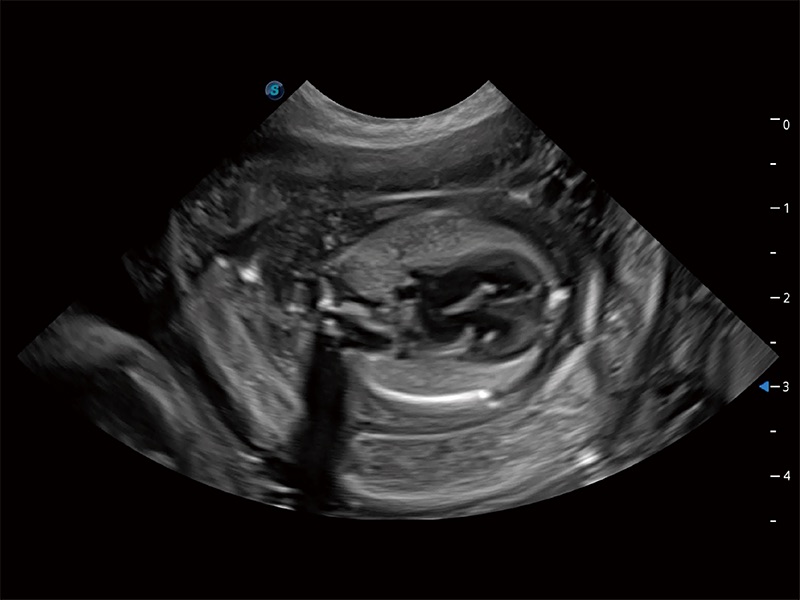

动物是人类最亲密的朋友和最值得信赖的伙伴。MILE米乐集团官网也一直致力于探索动物专用的超声影像解决方案。全新推出的ProPet系列,是MILE米乐集团官网在动物超声影像智能化、专业化、精准化的一次跨越式革新。动物不能用言语来表述自己的不适,通过超声影像,ProPet系列搭建了动物医生与不同物种沟通的“桥梁”,为动物医生注入了“治愈之力”。 ProPet 80 是MILE米乐集团官网匠心打造的一款高端动物专用彩超,采用性能卓越的全新硬件架构,极大提升超声系统的运行效率和数据处理能力,帮助动物医生从容应对日益增多的挑战性病例和日益多样化的临床需求。

高性能和先进的临床应用工具可以为动物医生提供临床信心。ProPet 80 搭载了先进的腹部和浅表应用工具,帮助医生在日常临床实践中发挥前所未有的作用。

ProPet 80 专为动物医生设计,对不同的动物体型和生理结构作出了针对性的优化。通过动物影像专用软件,可满足个性化的应用需求,帮助动物医生获得更精确的诊断数据。